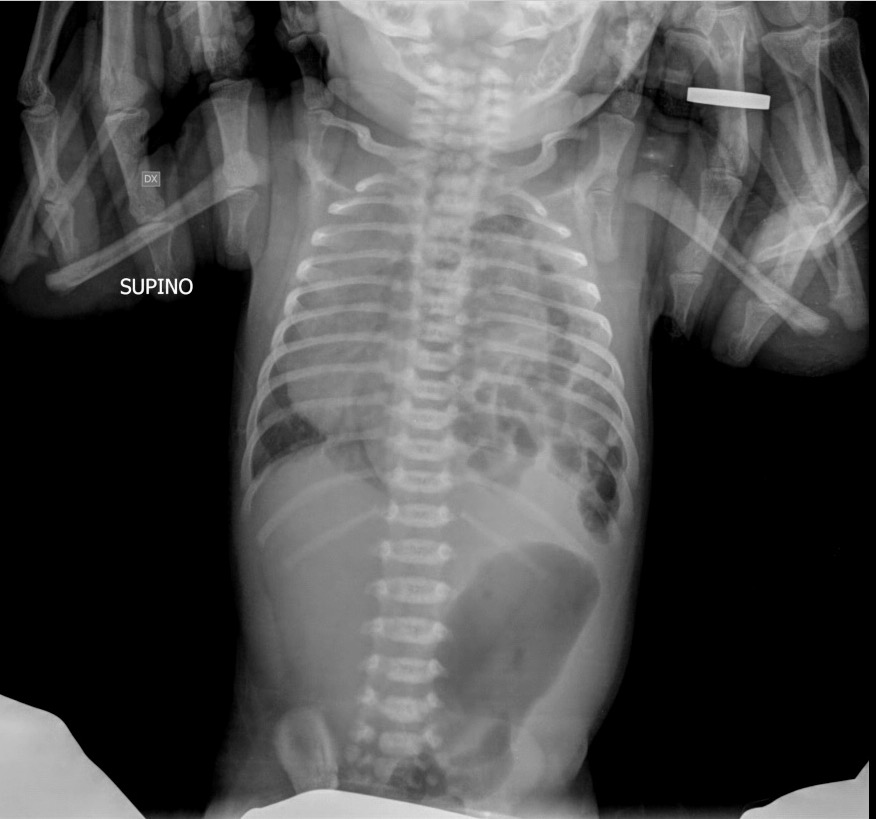

In sesta giornata si assiste a un drammatico scadimento delle condizioni generali; condotto in Pronto Soccorso presenta iporeattività, pallore, apiressia, tachidispnea (70 atti per minuto), tachicardia (180 bpm) con III tono udibile e saturazione O2 = 95%. Al torace murmure vescicolare assente e rantoli grossolani in basale sinistra. Addome trattabile. Si pratica in urgenza Rx torace: “emitorace sinistro occupato da multiple immagini aeree con cancellazione del profilo diaframmatico omolaterale; sbandamento mediastinico controlaterale” (Figura 1). Consulenza cardiologica con ecocardiografia: “Lieve scollamento pericardico; insufficienza tricuspidalica”.

Viene posta diagnosi di ernia diaframmatica congenita di sinistra e si ricovera in Terapia Intensiva Neonatale con ventilazione meccanica invasiva. Dopo 20 ore si esegue l'intervento chirurgico con reperto di erniazione in torace di ileo e colon trasverso, malrotazione intestinale, ischemia dell’appendice vermiforme. Dopo 48 ore: interruzione della ventilazione meccanica e inizio della nutrizione enterale. In nona giornata dimissione in equilibrio clinico con normalizzazione del reperto cardiologico.